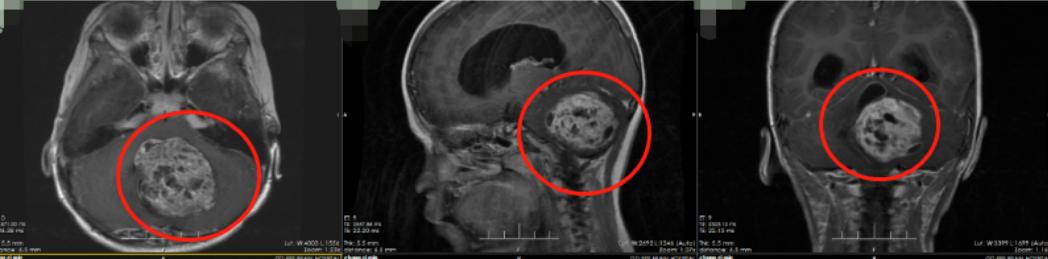

我院神经外二科主任林涛接诊了患儿。根据影像资料,林涛初步诊断为低级别胶质瘤可能,伴梗阻性脑积水,而且患儿已经出现慢性扁桃体下疝,精神状态极差,病情急重。

术前影像检查(脑干背侧可见巨大肿瘤,血供较为丰富)

完善相关检查,大外科首席专家陆永建教授和林涛主任带领团队进行了术前讨论,最终制定手术方案。1月18日,神经外二科在全麻下经枕下后正中入路为患儿行脑干背侧肿瘤切除术。